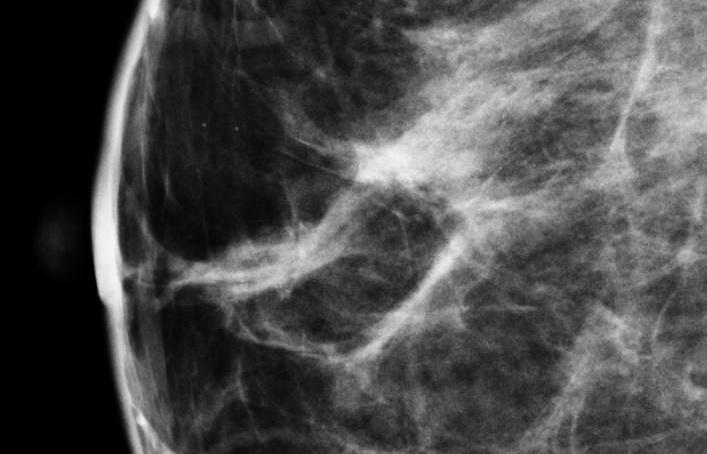

Approximately 40 percent of women have breast tissue categorized as dense, meaning relatively little fat and more connective and glandular tissue. Dense tissue can compromise the effectiveness of a mammogram and has also been cited as an independent risk factor for the development of breast cancer. As the American Cancer Society notes in Breast Cancer Facts and Figures, 2013-2014, “The risk of breast cancer increases with increasing breast density; women with very high density have a four to six fold increased risk of breast cancer compared to women with the least dense breasts.”